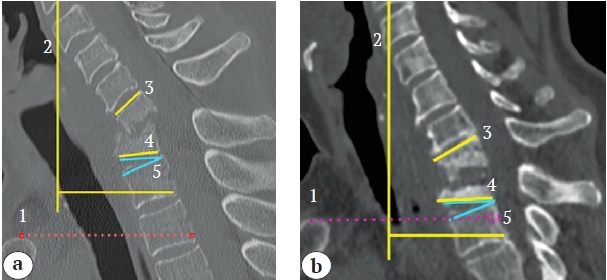

Preoperative preparation and anesthetic management were performed in all cases accor-ding to established recommendations, without clinically significant tactical deviations [24]. The planning of the ventral stage of reconstruction was based on sagittal CT scans. The necessity for manubriotomy was determined by drawing a horizontal line along the upper edge of the manubrium to the vertebral bodies, thereby defining the surgical trajectory for the access to the cervicothoracic spine. The planning scheme is shown in Figure 1.

Figure 1. Reconstruction planning scheme: sagittal CT scan showing surgical trajectory (1), cervical sagittal vertical axis C2-C7 (cSVA, 2), local kyphosis (LK, 3), T1 slope (T1S, 4), and neutral thoracic angle (NTA, 5): a — reconstruction without manubriotomy; b — manubriotomy required

To access the anterior column of the spine at the C6-T3 level, a right-sided oblique approach along the medial edge of the sternocleidomastoid muscle was used. The inferior boundary of the incision was limited by the sternoclavicular joint (in cases where the surgical trajectory was not obstructed by the manubrium) or extended to the lower edge of the manubrium if manubriotomy was required.

A common trend noted in the reviewed literature was the necessity of manubriotomy for reconstructing the cervicothoracic junction. However, none of the publications provide clear prognostic criteria for determining the need for this procedure [3, 6, 26, 27, 28, 29]. In our opinion, the trajectory of surgical accessibility, defined as a horizontal line drawn along the upper edge of the manubrium to the vertebral bodies, can serve as a universal tool for the preoperative planning of C6-T3 reconstruction in cases of chronic infectious spondylitis. This approach has consistently allowed for accurate prediction of the necessity for manubriotomy. A comparable tool is the cervicothoracic angle developed by H. Teng et al. However, its use is limited in case of infection due to the typical spread of paravertebral soft tissue components (abscesses and granulomas) requiring caudal mobilization of the anterior column, even for lesions in zones A and B [18].